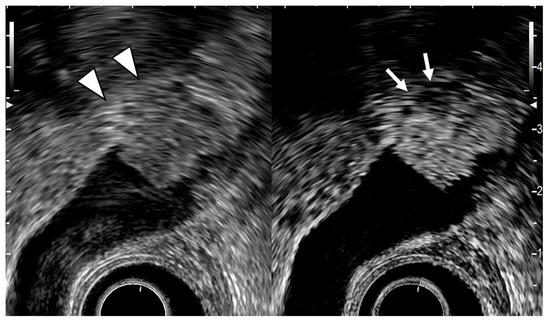

- Cho, J.H.; Park, J.Y.; Kim, Y.J.; Kim, H.M.; Kim, H.J.; Hong, S.P.; Park, S.W.; Chung, J.B.; Song, S.Y.; Bang, S. Hypoechoic foci on EUS are simple and strong predictive factors for neoplastic gallbladder polyps. Gastrointest. Endosc. 2009, 69, 1244–1250. [Google Scholar] [CrossRef]

- Sadamoto, Y.; Oda, S.; Tanaka, M.; Harada, N.; Kubo, H.; Eguchi, T.; Nawata, H. A useful approach to the differential diagnosis of small polypoid lesions of the gallbladder, utilizing an endoscopic ultrasound scoring system. Endoscopy 2002, 34, 959–965. [Google Scholar] [CrossRef]

- Choi, W.B.; Lee, S.K.; Kim, M.H.; Seo, D.W.; Kim, H.J.; Kim, D.I.; Park, E.T.; Yoo, K.S.; Lim, B.C.; Myung, S.J.; et al. A new strategy to predict the neoplastic polyps of the gallbladder based on a scoring system using EUS. Gastrointest. Endosc. 2000, 52, 372–379. [Google Scholar] [CrossRef]